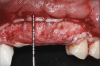

Fig 2. Buccal clinical view at baseline.

Figure 2

A systemically healthy 40-year-old male patient presented with a maxillary anterior vertical defect (Figure 1 and Figure 2). The patient stated that a previous bone grafting procedure was attempted in this area, but failed. The treatment plan involved a staged guided bone regeneration, the placement of three dental implants 9 months after bone augmentation, and soft-tissue grafting prior to implant loading to augment peri-implant soft-tissue thickness and keratinized mucosa width.